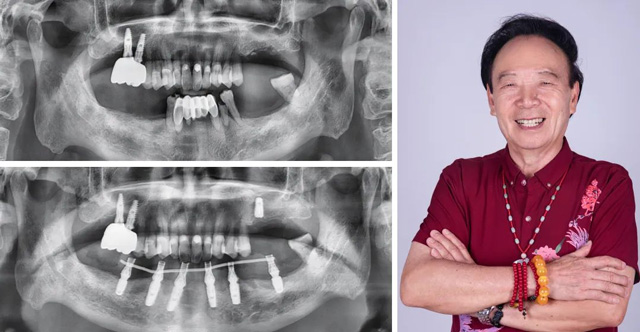

由于張叔叔下頜門牙牙根吸收較嚴(yán)重,保留意義不大,且他本人希望盡快恢復(fù)咀嚼功能。新橋醫(yī)療團(tuán)隊(duì)在對(duì)張叔叔的體檢報(bào)告進(jìn)行綜合評(píng)估,確保其能接受手術(shù)的情況下,新橋口腔成都衣冠廟院區(qū)種植??浦魅瓮跣駯|決定采用即拔即種的下半口種植修復(fù)方案。手術(shù)在張叔叔家人的陪伴下順利結(jié)束,同時(shí)醫(yī)院為張叔叔安裝了臨時(shí)牙冠,讓他能夠在當(dāng)天就恢復(fù)正常飲食。

“半口牙,兩個(gè)小時(shí)就給我整的巴巴適適、舒舒服服,我好像是枯枝發(fā)芽般得到了新生,仿佛年輕了20歲!”張叔叔笑道,“當(dāng)初和玉林那個(gè)醫(yī)生說,能不能拔了就立即種牙,他說我在做夢(mèng),現(xiàn)在我夢(mèng)想成真咯!”

在術(shù)后恢復(fù)階段,新橋口腔團(tuán)隊(duì)對(duì)張叔叔無微不至的關(guān)懷更是讓他感到無比安心與溫暖。僅四個(gè)月,張叔叔就正式戴牙,那些期盼了多年的美食,終于也能大快朵頤。